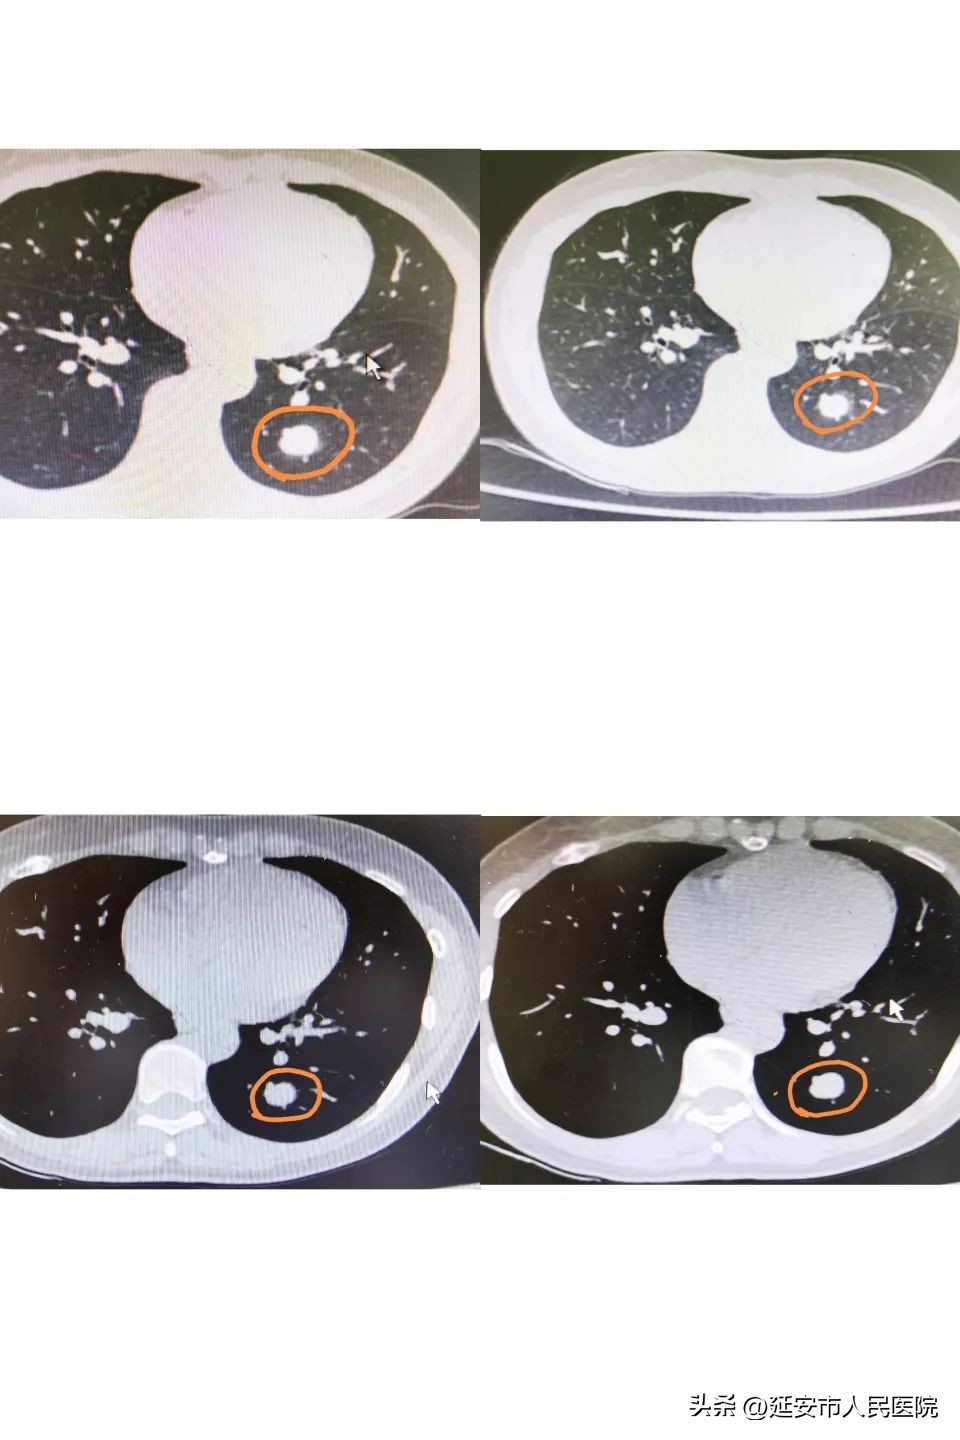

患者周女士,43岁,在当地县医院体检做胸部CT时发现左肺下叶一孤立结节影,当地医院建议去上级医院进一步检查。患者慕名来到我院呼吸与危重症医学科二病区专家门诊就诊,高院副主任医师接诊了患者,经过进一步检查,她分析:患者为青壮年女性,无吸烟史,无任何临床症状,结合胸部CT表现为一类圆形实性结节,边界清楚,无分叶征,无胸膜凹陷征,无毛刺,多考虑良性结节,但增强CT可见结节有强化,不能完全除外恶性结节可能,建议患者于我院肺结节MDT(多学科)门诊进行会诊讨论决定下一步诊疗方案。

经肺结节MDT专家组:孙萍主任医师、王启主任医师、张振显主任医师、高院副主任医师会诊后考虑:1.患者青年女性,无任何临床症状,无吸烟史,无肺癌家族史;2.胸部CT示左肺下叶可见一孤立类圆形结节影边缘清晰,密度均匀,无分叶征,无胸膜凹陷征,无毛刺,无肿大的肺门及纵膈淋巴结,增强扫描可见结节边缘血管贴边;多考虑为硬化性肺细胞瘤,建议外科手术切除。

王启主任介绍: 硬化性肺细胞瘤(PSP)是来源于呼吸道上皮的良性肿瘤,而非血管内皮、间皮来源和神经内分泌细胞来源。此瘤位于肺实质内,肿瘤主要有实性区、乳头状区、血管瘤样区、硬化区4种。本病多见于青、中年女性,右肺较左肺常见,尤以中叶和下叶为多,肿瘤位于肺部外周部,大多数无临床症状,少数有咳嗽、咯血。PSP影像学表现多为边缘清晰、圆形或类圆形单发软组织结节影,以肺周边多见,密度多均匀,多数形态规则,少数可见浅分叶,无深分叶征,无胸膜凹陷征及胸腔积液,无毛刺、空洞,无卫星灶,一般无肿大的肺门及纵膈淋巴结。增强扫描时肿块呈混杂性强化,强化特征主要与病变内的微血管密度有关。术前诊断困难,误诊率较高,有潜在恶性倾向,故外科手术是PSP唯一有效的治疗方法。